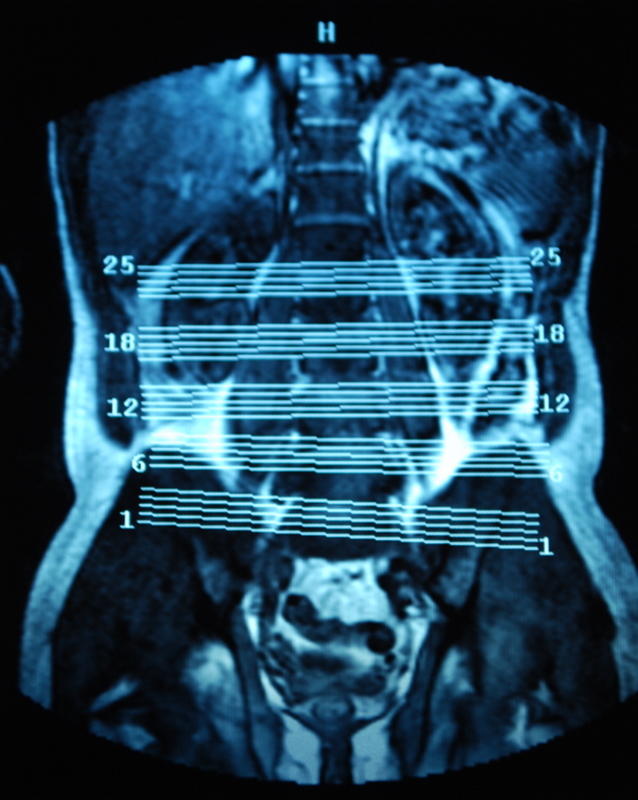

I’ve also come back with copies of my scans. Its very bizarre to sit there and look at slices through your own body. Forget losing weight so you look good in your holiday or wedding photos, try an MRI. There is no turning your best side to the camera or wearing stripes the right way round to hide/accentuate your curves. It shows all your fat, in lovely cross sectional detail. Cath also pointed out that she can see poo in some of the films! Nice…..

Apparently, I’ve also got a dehydrated disc on the next one up (L3/4) which might cause me issues in later life if I’m not careful with impacts, too.